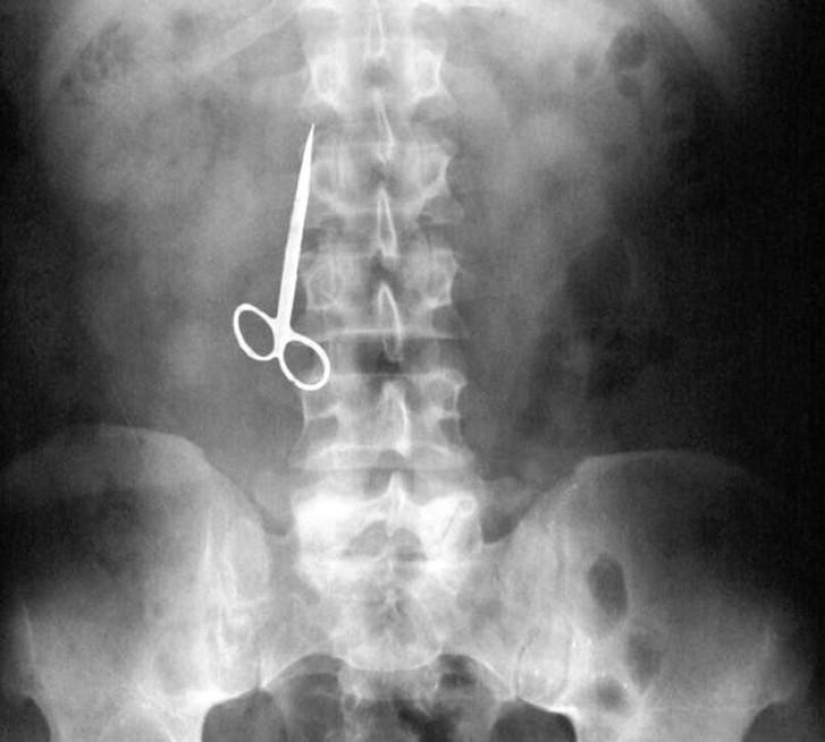

24. Tijera.